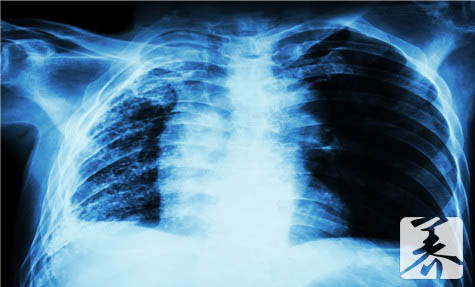

吃什么对肺子好